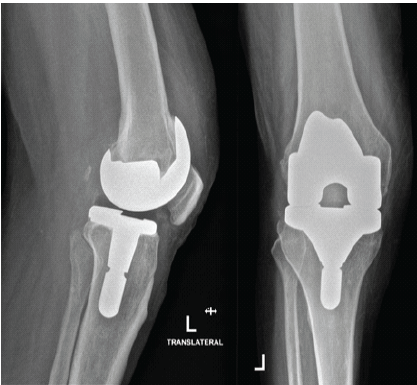

The patient was a 68-year-old male who had been diagnosed with type 2 diabetes, hypertension, and left leg peripheral arterial disease after a stent procedure in the left femoral artery. He first showed an infected left total knee prosthesis (Fig. 1).

Figure 1. Left knee after total knee arthroplasty. Anteroposterior and lateral radiographs demonstrating the left knee following primary total knee arthroplasty prior to the onset of infection.